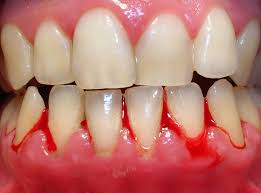

Nuestras propias investigaciones hechas con pacientes referidos a mi consulta para la búsqueda de focos dentógenos se cubren con las de Pritz. En el departamento clínico odontológico de la Caja de trabajadores pensionados de Viena donde soy jefe, valoré en 500 pacientes la prueba conjuntival de histamina según Remky. En todos aquellos casos sin contraindicación (iritis, conjuntivitis) busqué el valor promedio de reaccionabilidad (Glaser) de los dientes con tratamiento de conducto (Raab, 1961) Esta prueba se basa en el hecho de que a la presencia de focos o campos de interferencia en terreno de cabeza y cara, es decir: en el área dento-maxi-mandibular, aparece como signo de alteración del vegetativo una reacción de los vasos de la conjuntiva en el mismo segmento estimulado (terreno del trigémino) al colocar una solución diluida de la histamina. La respuesta positiva a esta prueba consiste en un enrojecimiento del ojo.

Se escogieron únicamente pacientes con las más diversas afecciones pertenecientes al círculo de enfermedades reumáticas, para ser más precisos: solo aquellas que fuera de dientes con tratamiento de conductos radiográficamente visibles, no presentaban ninguna otra clase de focos dentógenos potenciales y tampoco focos rinológicos. Esta limitación me pareció necesaria para no disminuir la fuerza comprobatoria de los resultados. El resultado de mis investigaciones era notable en el sentido de que de los 500 pacientes examinados 436, es decir la inmensa mayoría de esta colectividad tan cuidadosamente escogida y seleccionada (87.2%) presentó una reacción positiva mientras que la prueba solo salió negativa en 64 casos (12%). Esto comprueba que a la mayoría de todos los portadores de dientes con tratamiento de conducto les baste una pequeña sobrecarga adicional para romper la defensa local del foco dentógeno potencial y es de esta manera como se eleva la predisposición general a las enfermedades. Para evitar cualquier malentendido debo anotar que si la prueba de histamina sale positiva, esto no significa que podamos hablar entonces de una “dispersión” de los dientes que presenten pulpa muerta.

El test solo nos enseña que en tal sitio del vegetativo se ha roto la defensa local momentáneamente debido a la sobre carga aplicada. Si surge una sobrecarga más, bien sea ésta de naturaleza general o local y cae sobre este vegetativo agobiado focalmente, puede ser entonces que la insuficiencia, hasta el momento latente y en terreno de los inespecífico, se manifieste en forma clínica. Recapitulando lo dicho sobre el problemático papel que juegan los dientes con pulpa muerta en suceso focal, especialmente aquellos con tratamientos de conducto, sale de alli según nuestra opinión y para la práctica odontológica la siguiente enseñanza: “Un tratamiento de conducto es naturalmente aceptable en paciente sano, tolerable – tal vez- en el portador de focos considerado aun como sano, si es que se puede usar aun esta expresión! Empero...como terapia en si no se justifica de ninguna manera en enfermos agobiados por focos o en enfermos en los que ya fracasaron los mecanismos de la defensa vegetativa de todo el organismo. Hay que tener siempre presente el hecho de que aun no se ha logrado desarrollar un método de tratamiento de conductos capaz de evitar una enfermedad focal dentógena o por lo menos de influenciar benéfica y permanentemente una que ya se haya manifestado. “Sabemos que el principio patogenético del diente con pulpa muerta se basa en la sensibilización y alergización del cuerpo, por descomposición protéica, la que muy a pesar del mejor relleno de canales se abre a paso a través de los canalículos transversales desde el interior del diente hasta el periodoncio y desde allí hacia todo el organismo” Pritz, 1964, Raab, 1964.